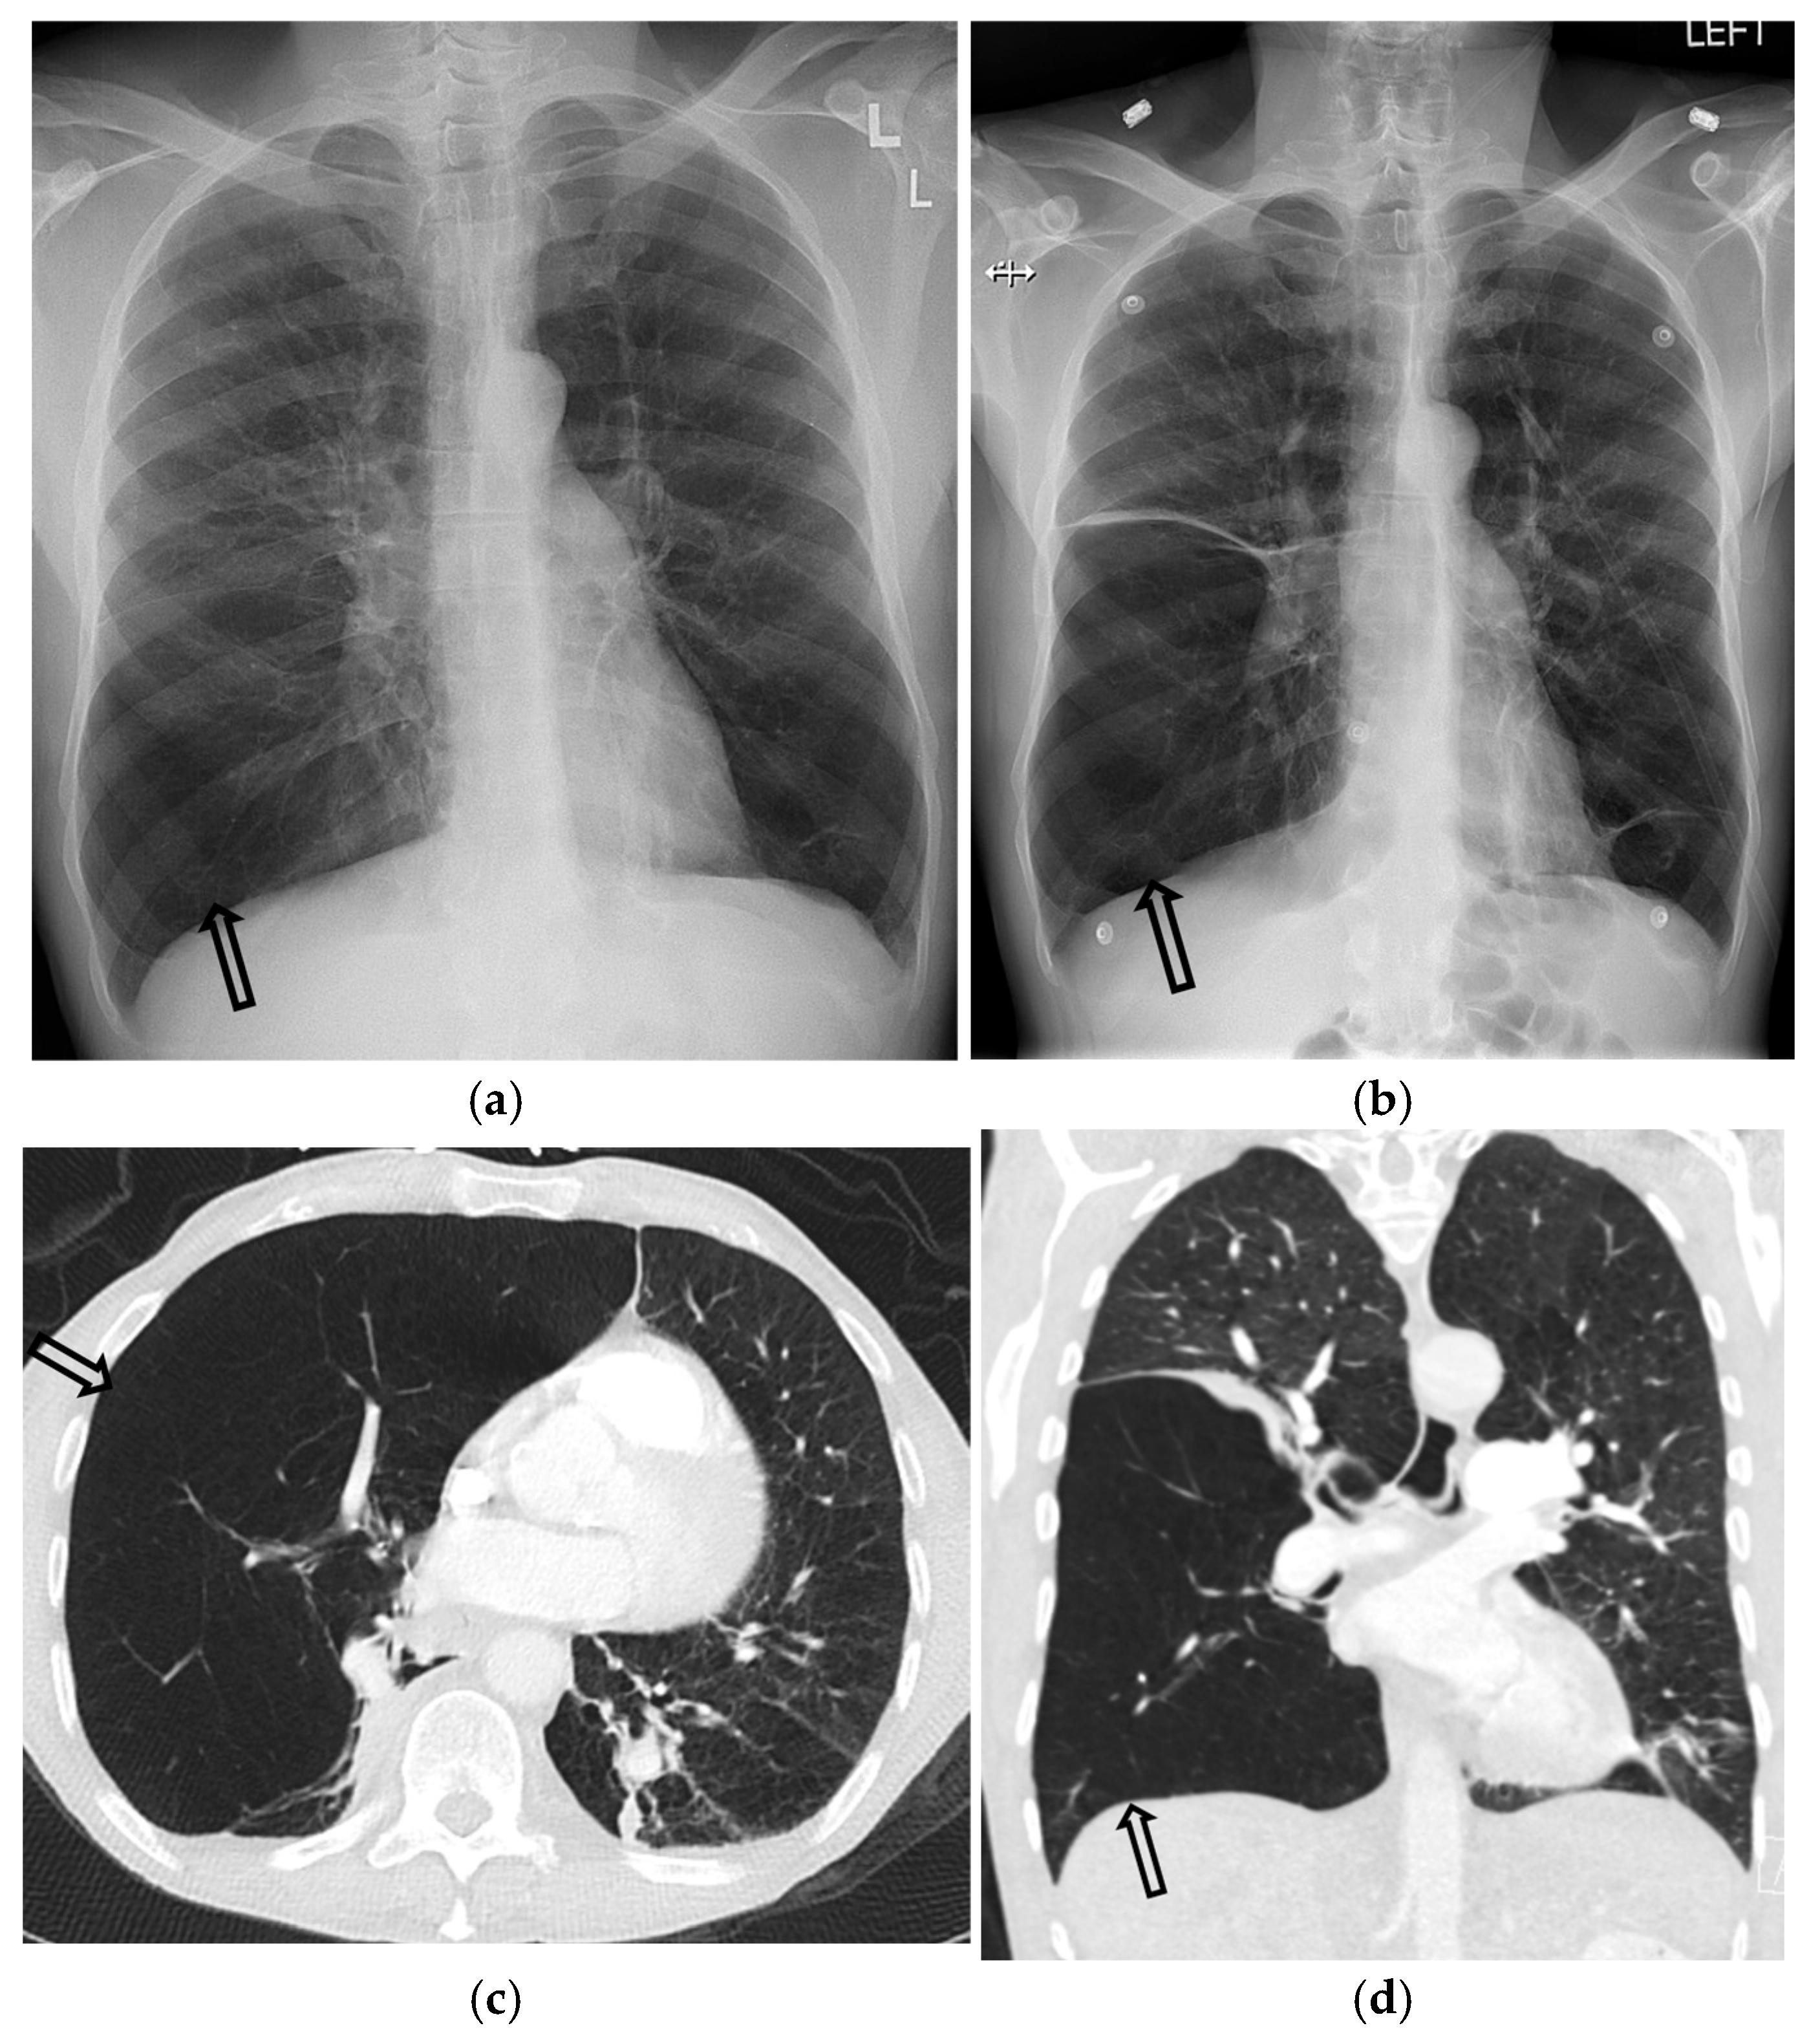

3.1. Chest Radiography

4.1. Chest Radiography Pitfalls